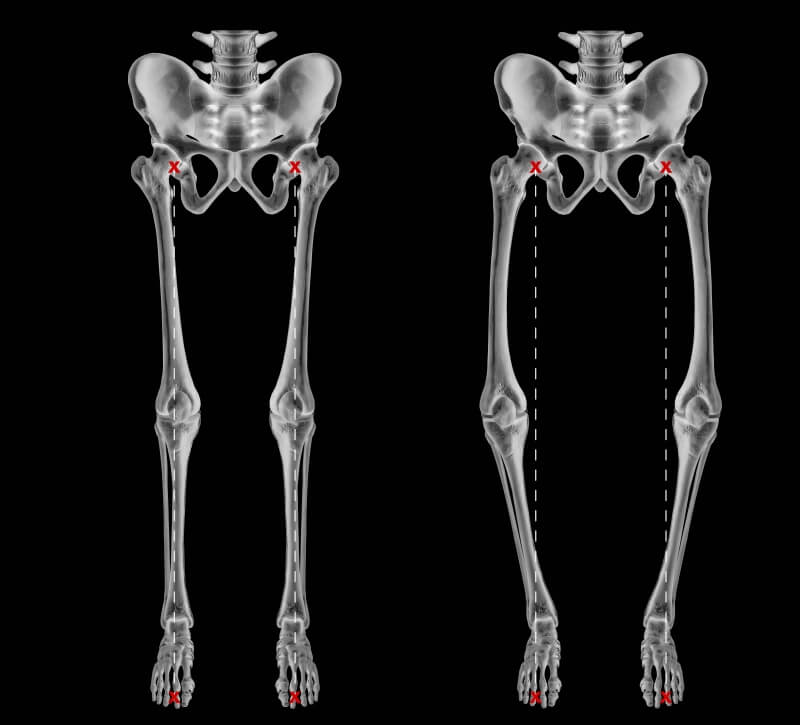

Knock Knees, also known as genu varum, is a condition where the legs appear bowed outwards when standing. This condition can cause discomfort, pain, and even difficulty walking. In severe cases, surgery may be required to correct the alignment of the legs. In this article, we will discuss the causes, symptoms, and treatment options for Knock Knees, including the various surgical procedures available.

A doctor can diagnose knock knees by performing a physical examination and assessing the alignment of the legs. Imaging tests such as X-rays or MRI scans may also be used to confirm the diagnosis.